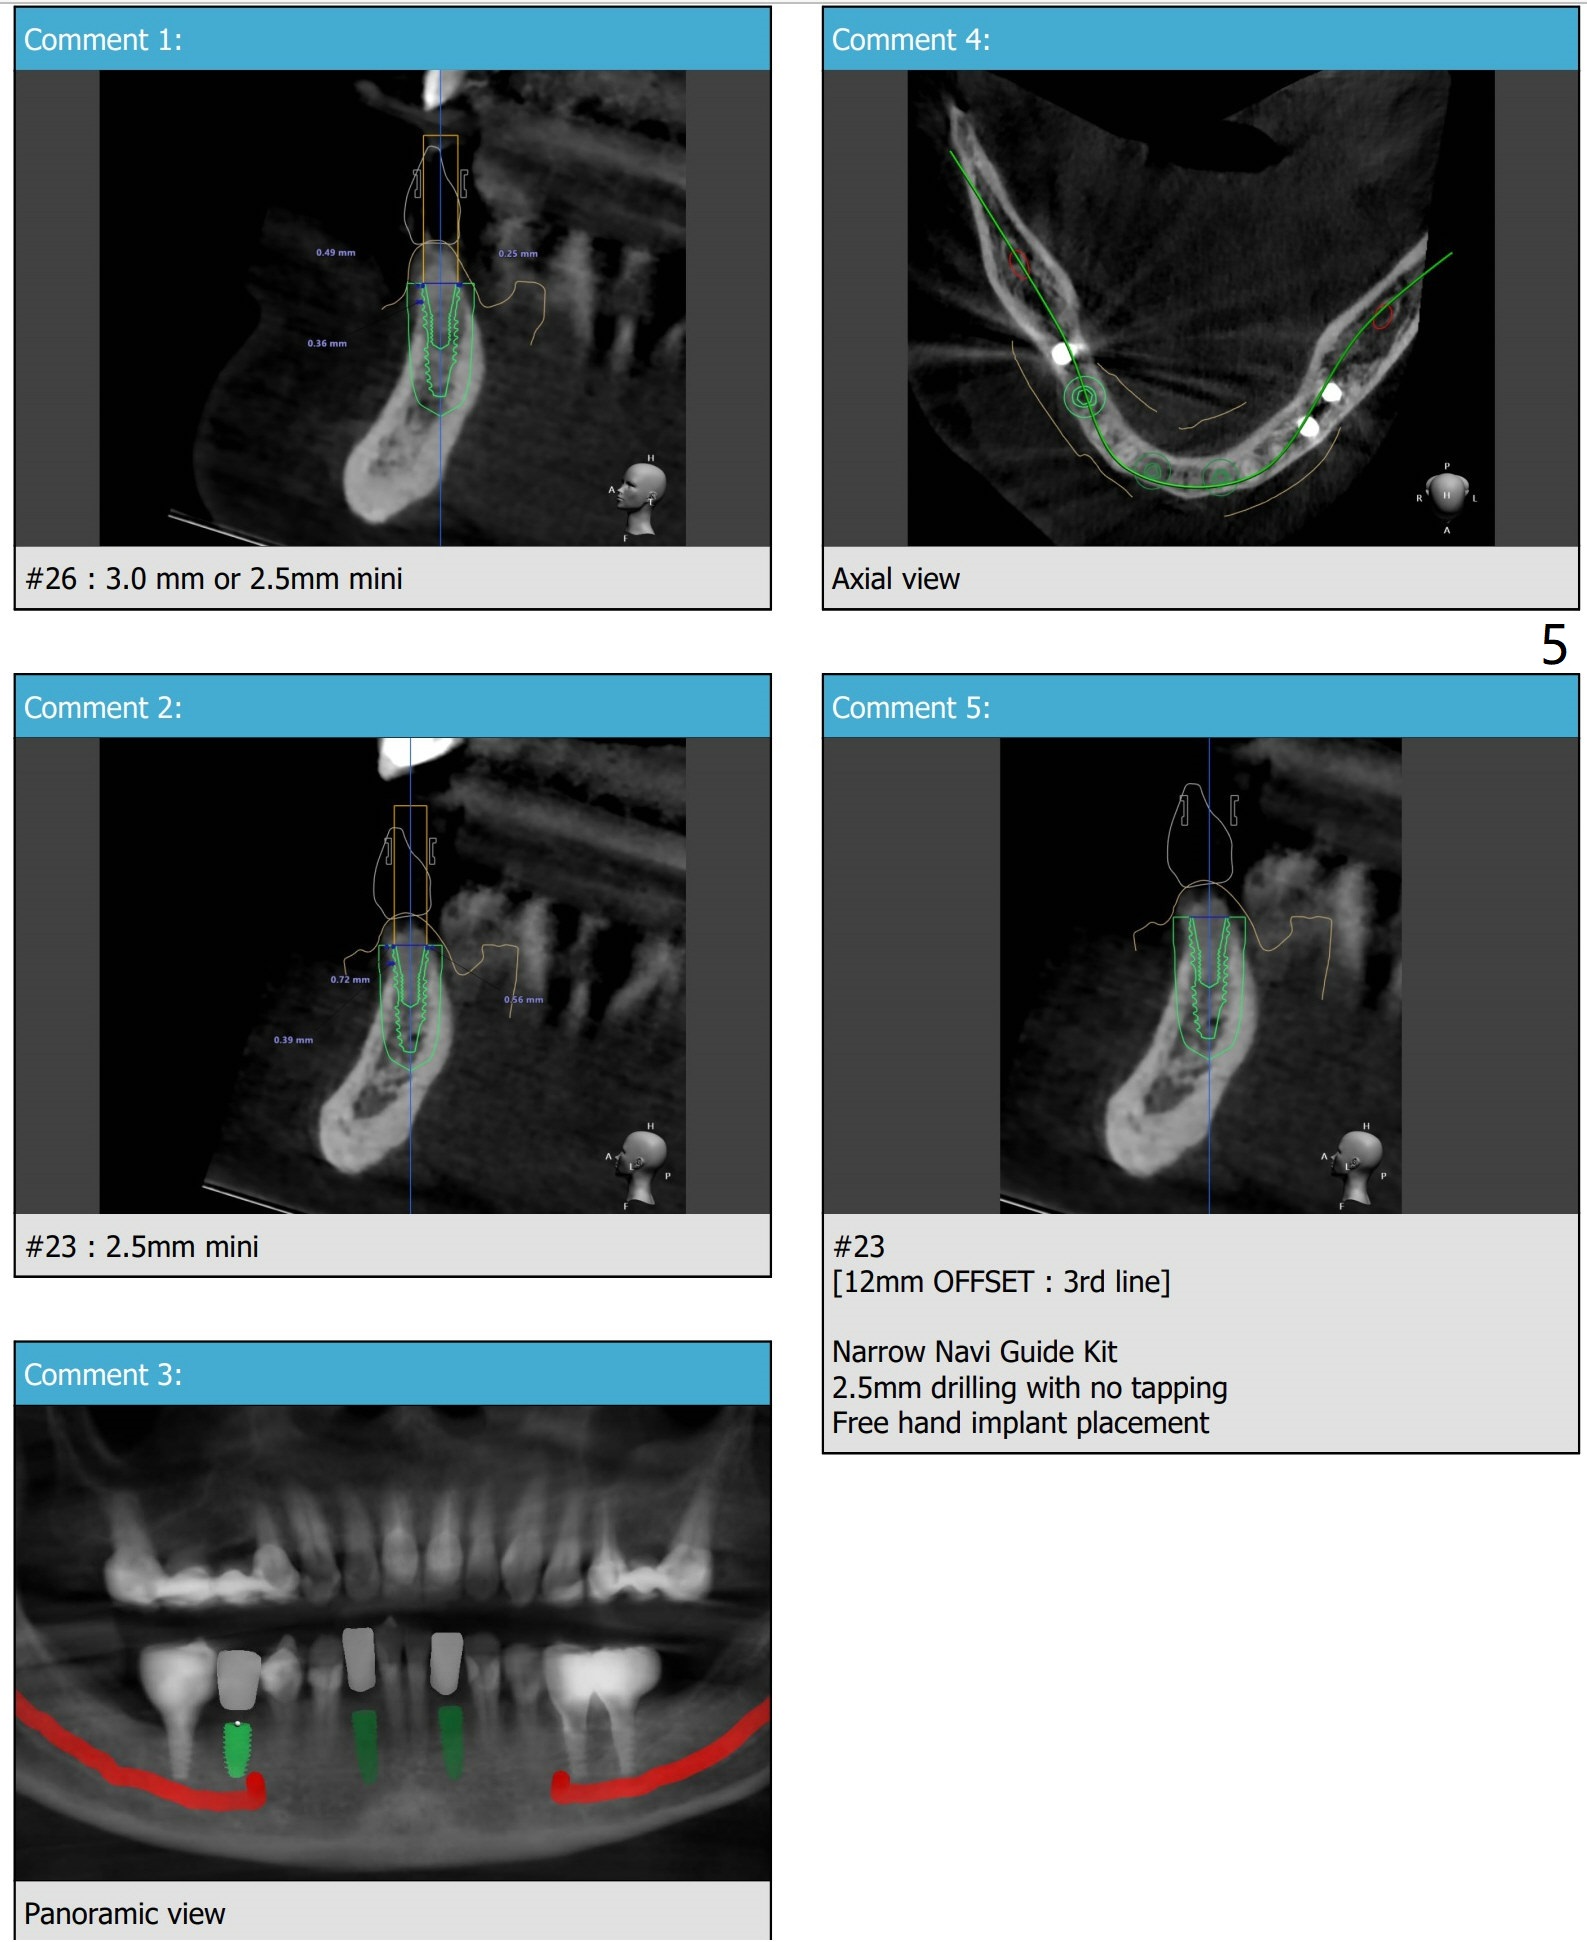

导板钻洞徒手植入

57岁女